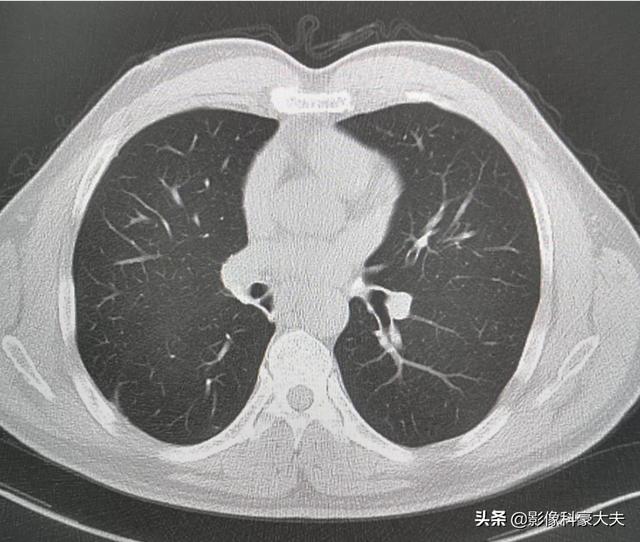

Eine sublobeare Resektion (d. h. eine segmentale Resektion oder Keilresektion) hat weniger Auswirkungen auf die Lungenfunktion, da weniger Lungengewebe entfernt wird und mehr normales Lungengewebe verbleibt. Wird eine Lobektomie durchgeführt, weil mehr Lungengewebe entfernt wird, verbleibt relativ wenig normales Lungengewebe, was sich stärker auf die Lungenfunktion auswirkt und eher zu Beschwerden in der Brust führen kann. Die folgenden Bilder zeigen die Lungen von zwei verschiedenen Resektionen: Das obere Bild zeigt die Lobektomie des rechten unteren Lungenknotens, und Sie können sehen, dass die rechte Lunge nach der Operation deutlich kleiner ist. Das untere Bild zeigt eine sublobar Resektion des linken unteren Lungenknotens, und Sie können sehen, dass die linke Lunge nach der Operation ein größeres Volumen aufweist.